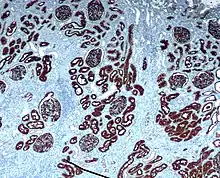

Immunohistochemistry (IHC) is the most common application of immunostaining. It involves the process of selectively identifying antigens (proteins) in cells of a tissue section by exploiting the principle of antibodies binding specifically to antigens in biological tissues.[1] IHC takes its name from the roots "immuno", in reference to antibodies used in the procedure, and "histo", meaning tissue (compare to immunocytochemistry). Albert Coons conceptualized and first implemented the procedure in 1941.[2]

- Chromogenic immunohistochemistry (CIH), wherein an antibody is conjugated to an enzyme, such as peroxidase (the combination being termed immunoperoxidase), that can catalyse a colour-producing reaction.[3]

Reporter molecules vary based on the nature of the detection method, the most popular being chromogenic and fluorescence detection mediated by an enzyme or a fluorophore, respectively. With chromogenic reporters, an enzyme label reacts with a substrate to yield an intensely colored product that can be analyzed with an ordinary light microscope. While the list of enzyme substrates is extensive, alkaline phosphatase (AP) and horseradish peroxidase (HRP) are the two enzymes used most extensively as labels for protein detection. An array of chromogenic, fluorogenic and chemiluminescent substrates is available for use with either enzyme, including DAB or BCIP/NBT, which produce a brown or purple staining, respectively, wherever the enzymes are bound. Reaction with DAB can be enhanced using nickel,[9] producing a deep purple/black staining.

After immunohistochemical staining of the target antigen, a second stain is often applied to provide contrast that helps the primary stain stand out. Many of these stains show specificity for specific classes of biomolecules, while others will stain the whole cell.[3] Both chromogenic and fluorescent dyes are available for IHC to provide a vast array of reagents to fit every experimental design, and include: hematoxylin, Hoechst stain and DAPI are commonly used.